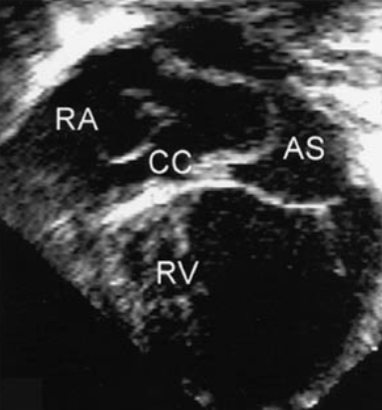

Chiari Network

a freely mobile, lace/mesh-like membrane

located in RA near orifice of coronary sinus

embryonic remnant

similar to Eustachian

seen in 2-3% of the pop

needs to be DDX’d from mass or tumor